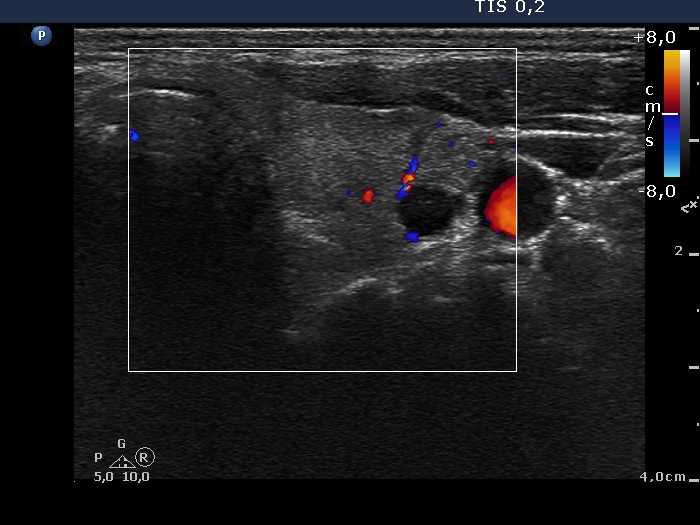

Right lobe, longitudinal scan

Left lobe, transverse scan, color Doppler mode. The vascularization is not specific.